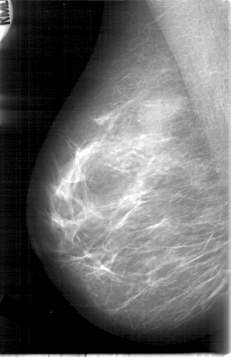

D_4006_1.RIGHT_MLO

RIGHT_CC LINES 5296 PIXELS_PER_LINE 3526 BITS_PER_PIXEL 12 RESOLUTION 43.5 NON_OVERLAY

RIGHT_MLO LINES 5341 PIXELS_PER_LINE 3451 BITS_PER_PIXEL 12 RESOLUTION 43.5 NON_OVERLAY